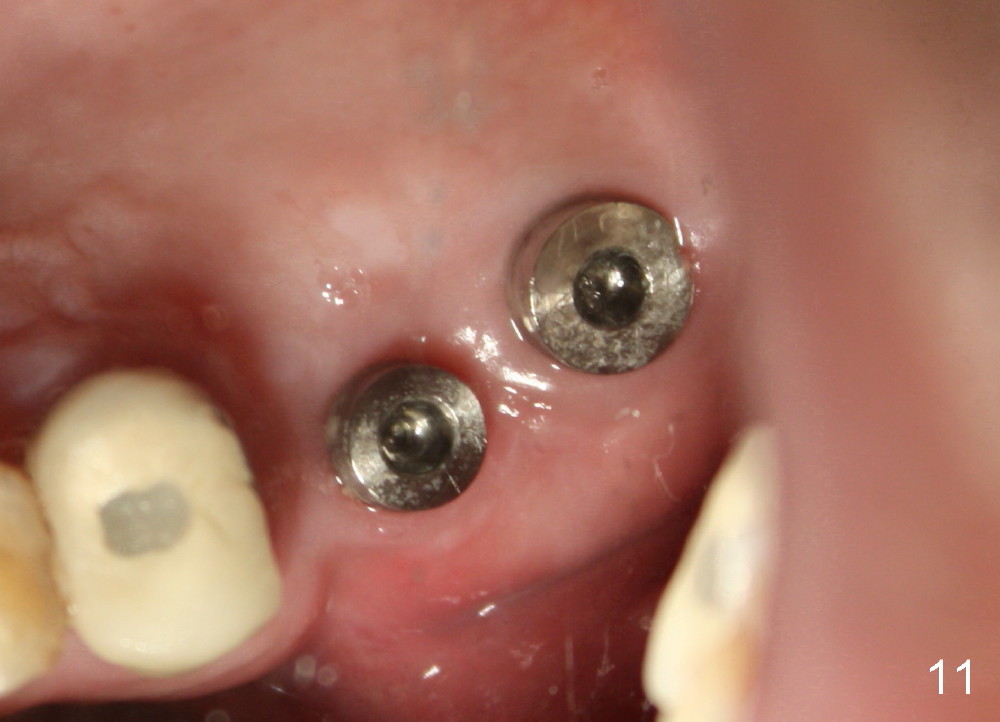

![]() |

Three months and a half postop, there is bone growth in the previous mesiobuccal socket (Fig.10 (B), compare Fig.5,7). Soft tissue also heals (Fig.11). Using a larger implant (7 mm in diameter) may facilitate wound healing (Fig.12, as compared to Fig.2).